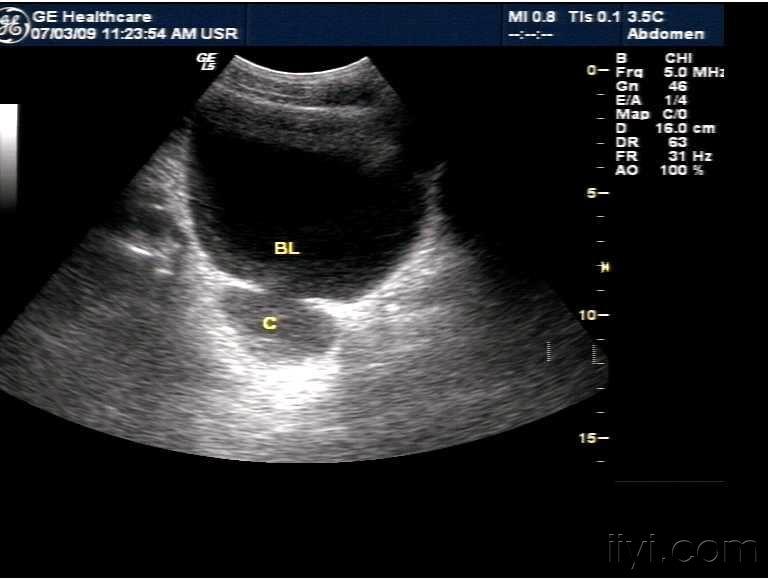

膀胱憩室. - 超声医学讨论版 - 爱爱医医学论坛

图片尺寸770x580